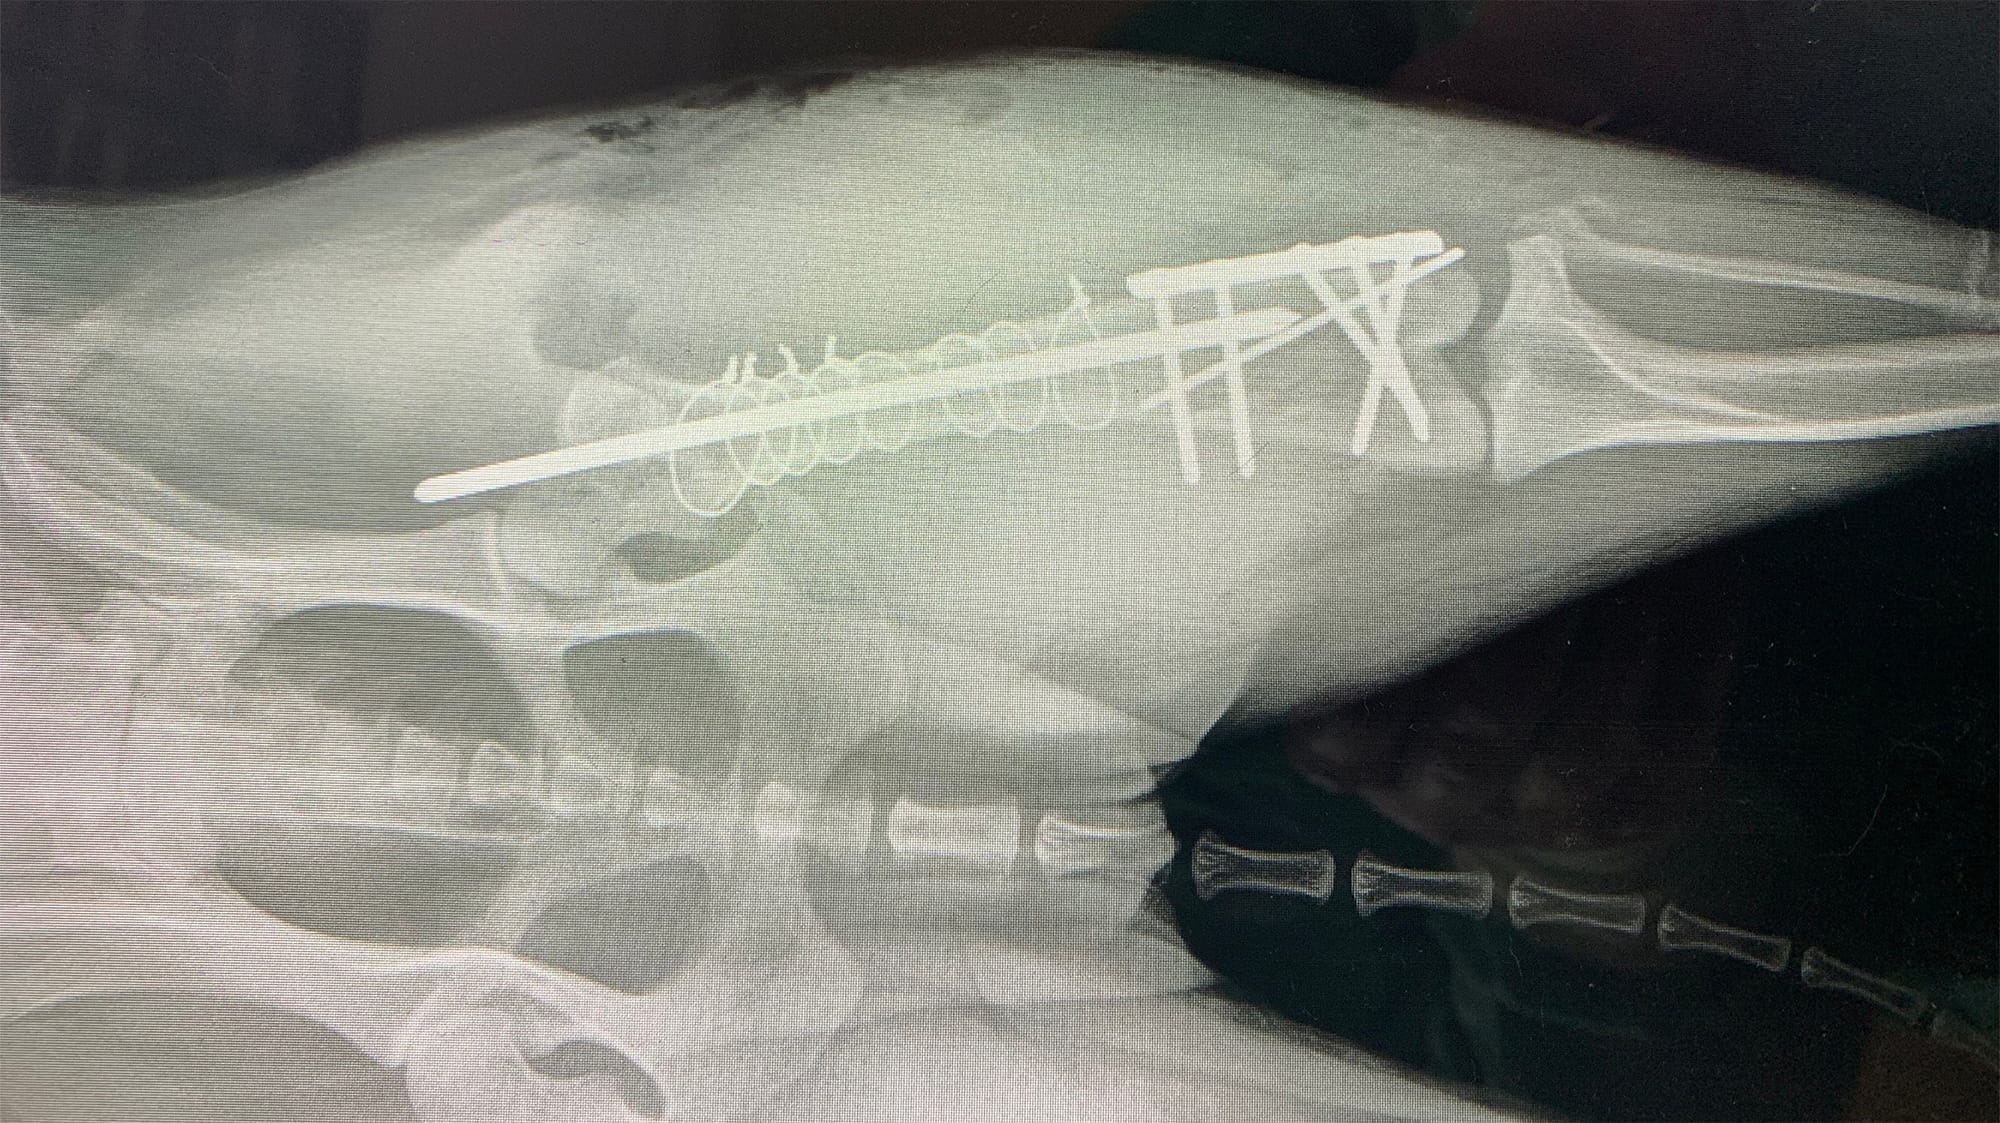

Dr. Beckett confirmed it: He does love a challenge, and Chevy’s leg was just that. Multiple parts of the femur (the thigh bone) were fractured, including the condyle which is part of the knee joint. The X-ray showed three clear breaks, but they ran both up and down as well as side to side. During the one-hour-and-45-minute surgery, however, Dr. Beckett and a young veterinarian discovered seven breaks. Their surgical team used stainless steel metal implants to stabilize the multiple pieces of bone. In the end, Chevy would need extensive surgery to repair the fractures and stabilize the knee joint. Dr. Beckett and his team made it happen with an assortment of medical implants, including rods, plates, screws and wires.